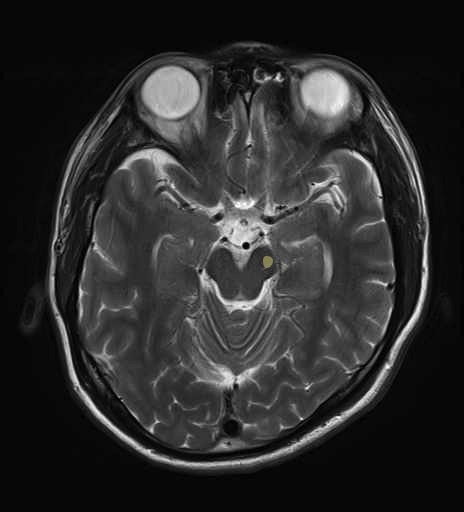

錐体路・皮質脊髄路のMRI画像解剖

■皮質脊髄路(いわゆる錐体路):一次運動野から脊髄遠隔の下位運動ニューロン細胞体まで

■皮質核路:一次運動野から橋及び脊髄神経核まで